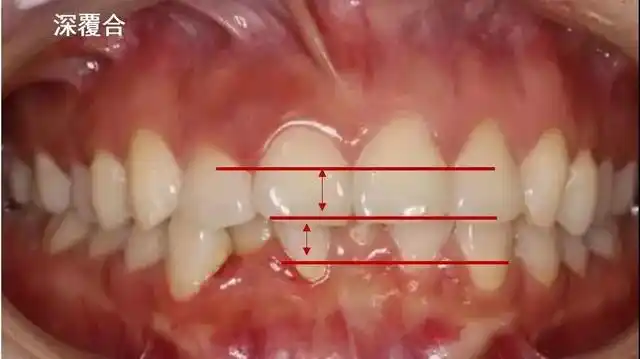

也就是说,如果 上牙包住下牙的范围超过了2~3mm,就是深覆合.